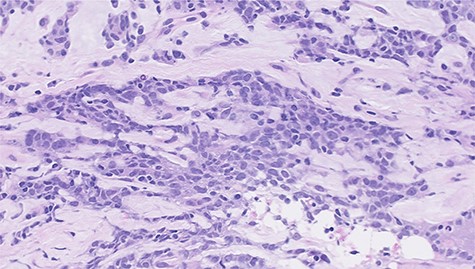

Histopathological features of left breast tumor. The biopsy specimen demonstrated invasive carcinoma with features of metaplastic carcinoma, i.e. without ductal structure, with tumor cell matrix-producing or some spindle cell characteristics (hematoxylin and eosin stain, ×400).